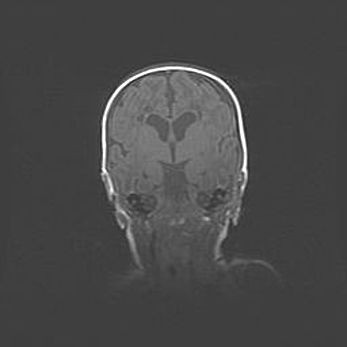

Ниже представлена  галерея МРТ снимков, полученных с применением LMT неонатальных матричных РЧ катушек. Также каждая группа МРТ снимков сопровождается информацией о пациенте (диагноз, возраст, вес, пол, срок гестации) и краткой сопроводительной расшифровкой диагноза.

Наружная гидроцефалия с возможной атрофией височных областей.

Возраст: 28 дней

Вес: 3670 г

Пол: мужской

Окружность головы: 38 см

Срок гестации: 40 недель

Гидроцефалия головного мозга у новорожденных – это заболевание, которое характеризуется скоплением избыточного количества спинномозговой жидкости в желудочковой системе головного мозга в результате затруднения её перемещения от места выработки к месту поглощения в кровеносную систему или вследствие нарушения абсорбции. При открытой наружной форме гидроцефалии у новорожденных расширяются и переполняются субарахноидные пространства.

При нормотензивных  формах,  которые,  как  правило,  являются  следствием  перенесенных ишемических  повреждений  паренхимы  мозга,  возможно  сочетание микроцефалии  с нормотензивной гидроцефалией. В основе данных изменений лежит атрофия больших полушарий с преимущественной  локализацией  в  лобно-височных  областях.